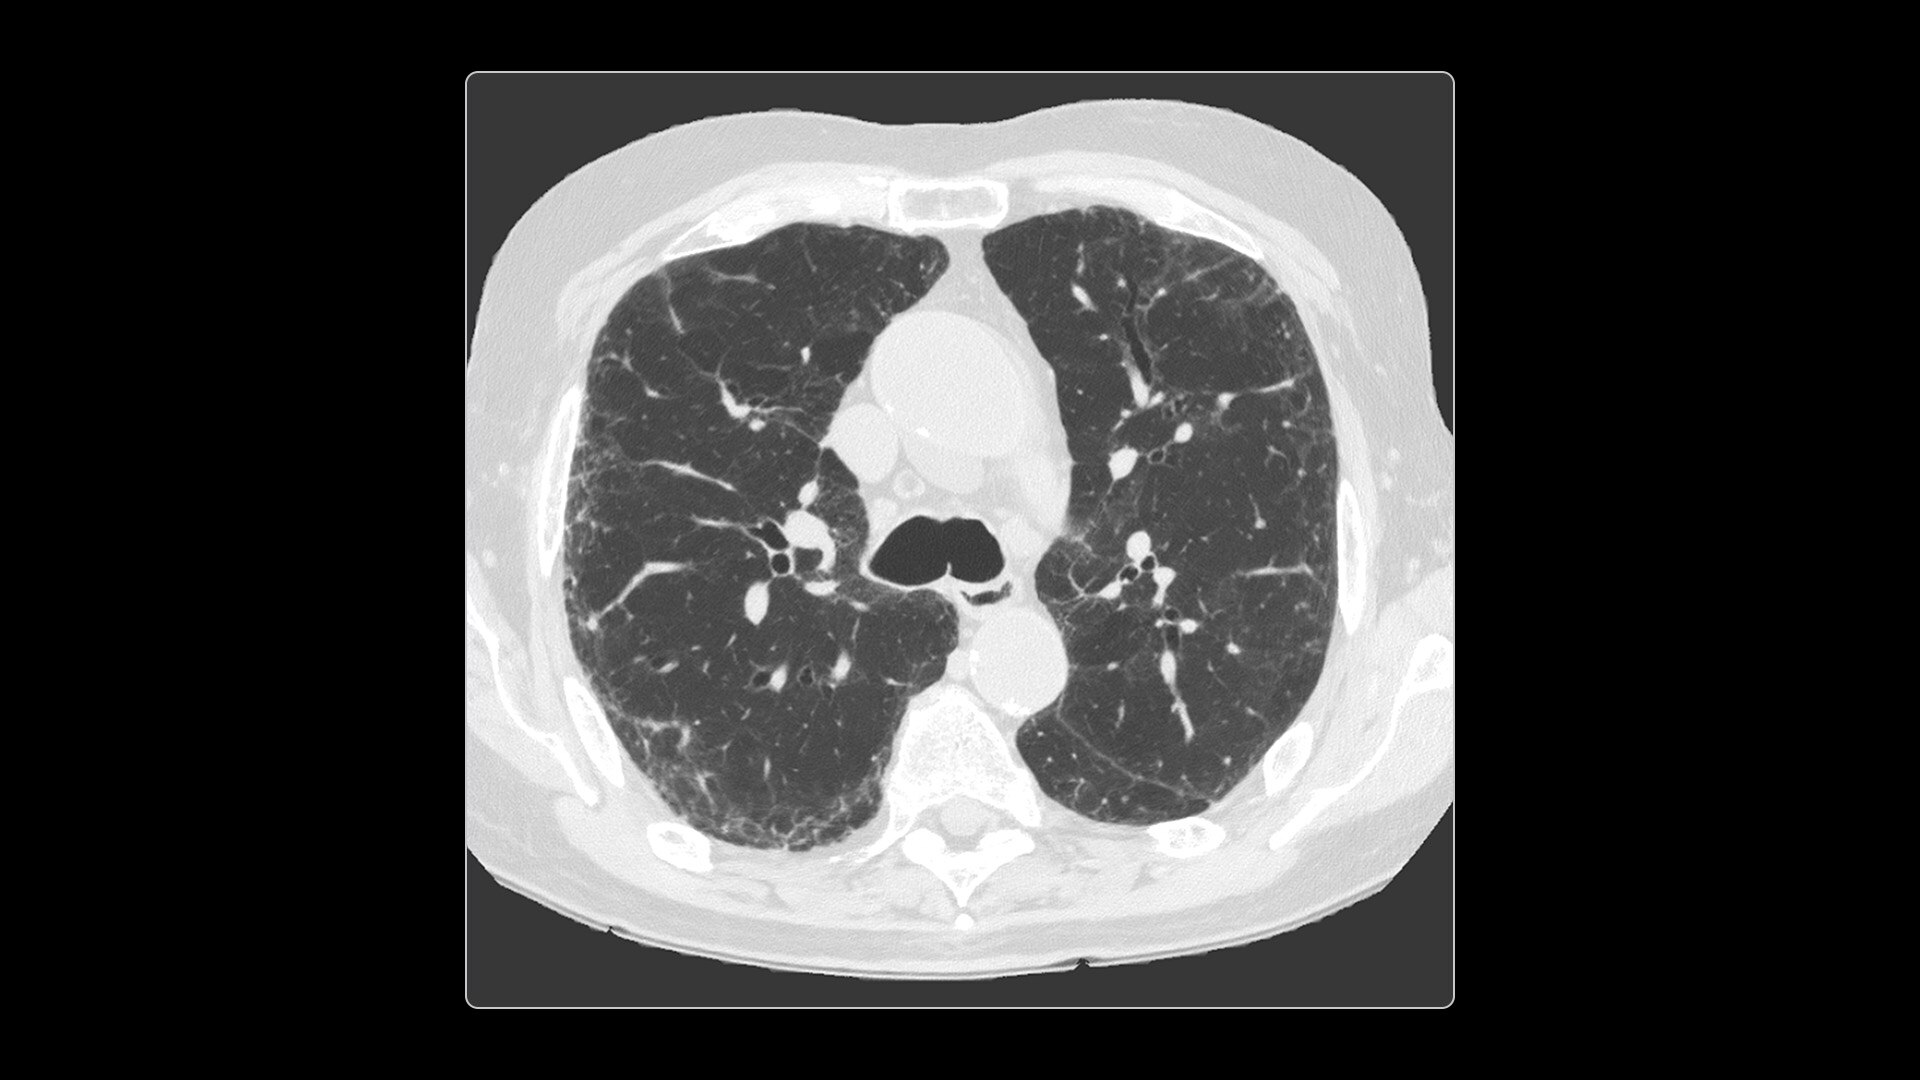

Photonova Spectra provides wide coverage in ultra-high definition imaging with exceptional acquisition speeds, designed to allow you to see your patient’s anatomy in exquisite detail.

With ultra-high spatial resolution scanning capability, Photonova Spectra is designed to help you see incredibly fine details, such as coronary plaque delineation, small microvascular vessels and even tiny structures of the inner ear.

Experience our industry-leading 8 cm detector coverage, combined with up to 0.23 sec rotation speed and ultra-high sampling rates featuring a 50 cm field of view (FOV) in all scan modes. This enables wide-coverage ultra-high definition imaging with reduced organ movement for exceptional image clarity.